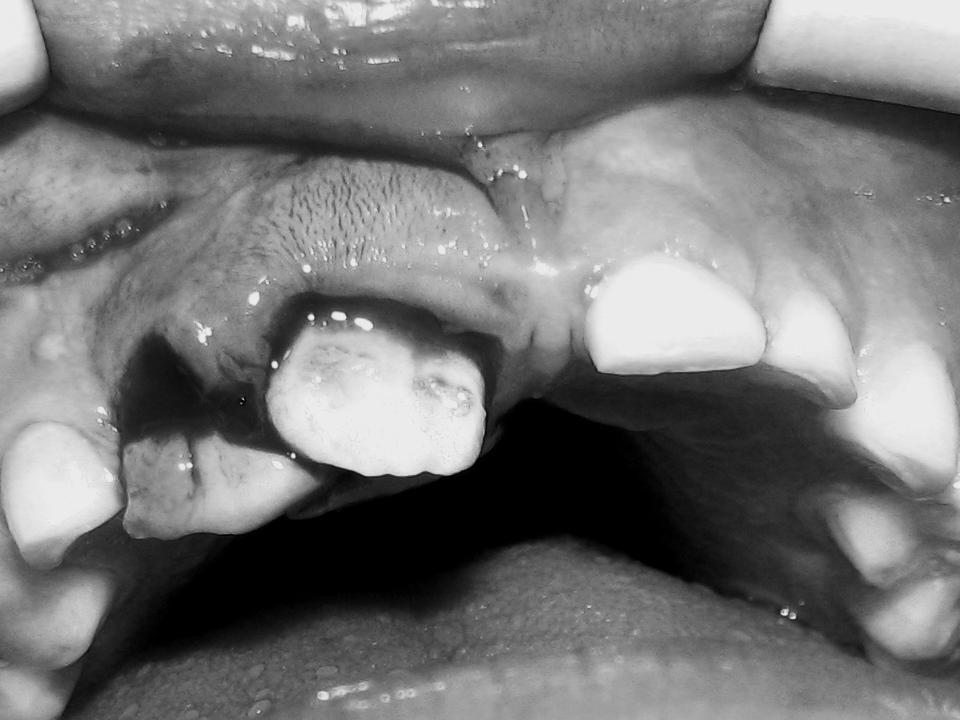

Corona de diente permanente fracturado o astillado: La acción rápida puede salvar el diente, prevenir la infección y reducir la necesidad de tratamiento dental extenso. Enjuagar la boca con agua y aplicar compresas frías para reducir la hinchazón. Si es posible, localizar y guardar los fragmentos de diente roto y llevarlos a nuestra clínica.

Corona de diente de leche fracturado: Trae inmediatamente a tu hijo a la consulta para evaluar si es posible conservarlo.